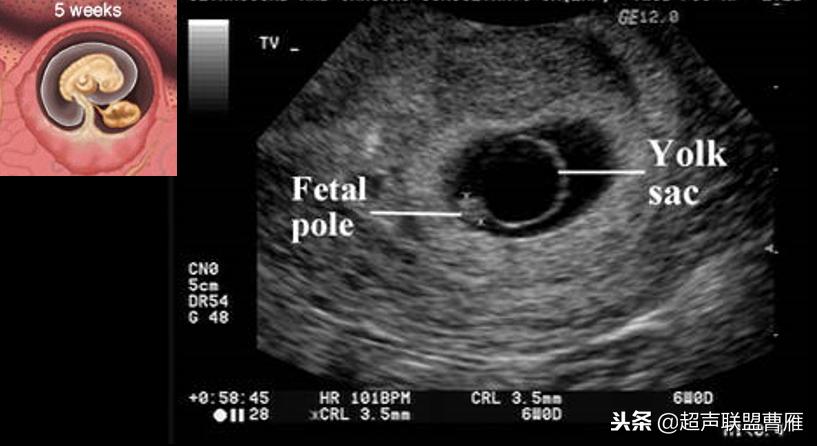

妊娠40天,见到卵黄囊、胚极及心管搏动, HCG12800U/L。

妊娠35天,高分辨的超声检查就可能见到心管搏动、胚极及卵黄囊。

5周+ 、6周+ 声像图

早孕 胚芽 卵黄囊